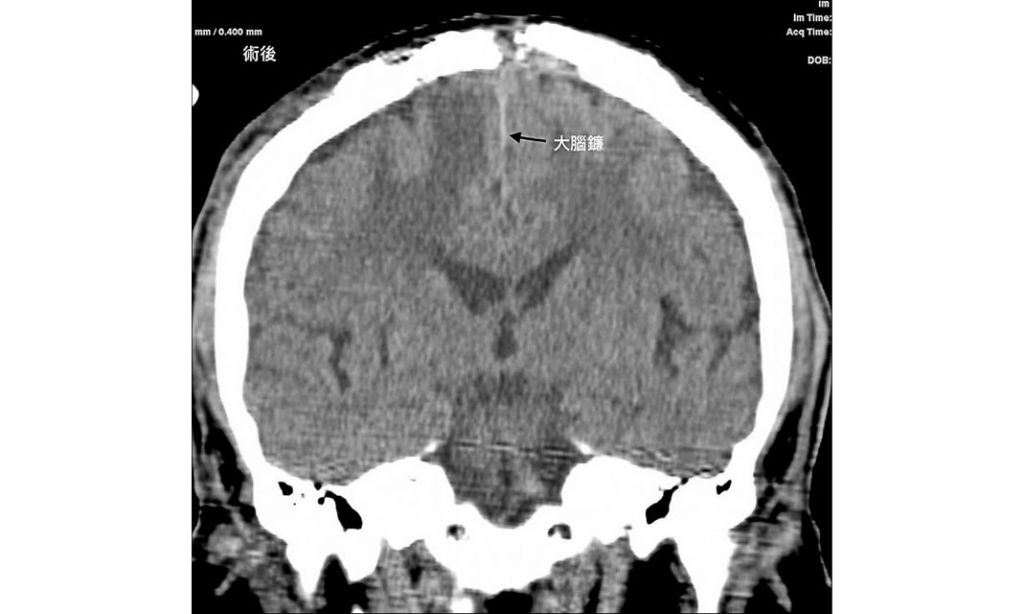

結果發現一個位在中線的大腦鐮腫瘤,進一步做核磁共振檢查之後,判斷是一個直徑6公分而且跨越中線的大腦鐮腦膜瘤合併雙側前額葉的腦水腫 (圖1)。因此,我們進行雙側前額葉的開顱手術把腫瘤從兩邊切除(圖2)。

阿春伯術後很快恢復清醒跟下肢的力量,雖然走路依然遲緩;但是他那神秘的微笑在術後並沒有消失,也許是漫長的腫瘤生長過程已經對大腦前額葉造成傷害,或許要更長的時間才能恢復。